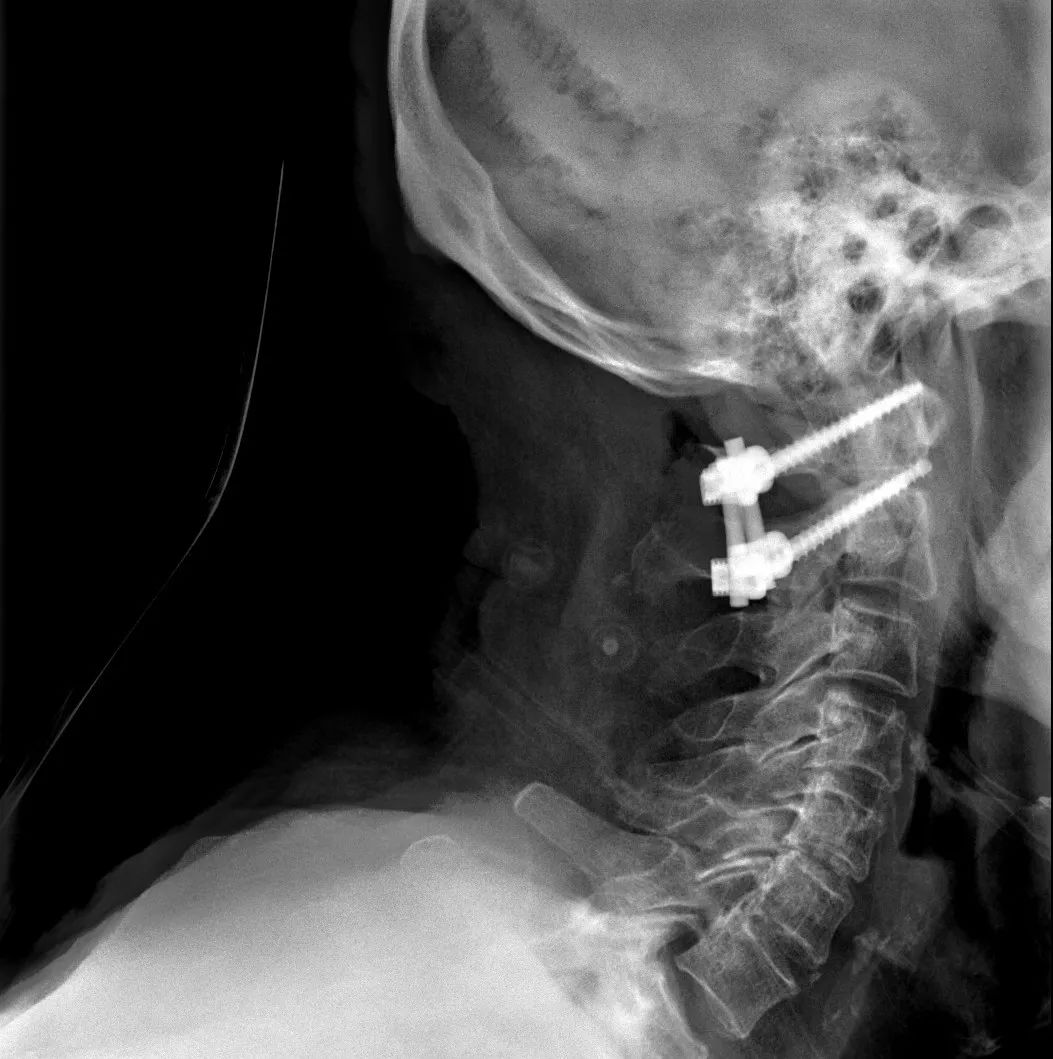

患者经充分咨询了解,选择了枣庄市立医院脊柱外科主任王存平为其治疗。面对患者和家属期盼的目光,王存平明白这是患者最后的希望,故而没有胆怯和退缩,大胆提出了齿状突骨折后路切开复位C1、2椎弓根钉棒系统固定的手术方案。由于患者年龄较大,存在脊柱严重后凸畸形,俯卧位极度困难,全麻插管难度大,麻醉风险极大。麻醉科李传东和宓云飞医师克服重重困难,成功完成麻醉。在他们得力的麻醉和监护下,王存平仔细分离、细心操作,每一步都确保动作稳稳完成,最终成功实施了手术。

经过全程监护和系统治疗,患者术后恢复良好,骨折解剖复位,复查X线及CT显示固定位置佳,术后3天下地行走,术后4天即出院回家休养。

该手术为我市首例完成C1、2椎弓根钉棒系统固定手术,填补了枣庄在上颈椎外伤手术史上的空白,展现了枣庄市立医院脊柱外科不怕困难、勇于突破、积极向上的精神面貌,也是王存平主任技术高超、胆大心细的具体体现。